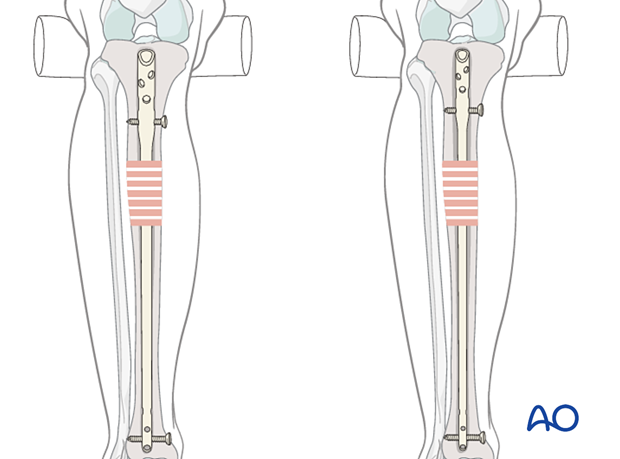

The diameter of the tibial medullary canal varies between 13 mm and 8 mm or less. Reamers can be used to enlarge the medullary canal for larger diameter nails. Such nails permit larger diameter locking screws. The strength and durability of screws and nails increases with their diameter. The medullary canal should be reamed so that it is slightly larger than the intended nail diameter (usually about 1.5 mm more), to ease nail insertion. The image illustrates a non-reamed nail on the left, and a reamed nail on the right. Stability is increased with the reamed technique, because the nail fits snugly in a longer portion of the tibial shaft.

Reaming is currently favored for most tibial nailing, but this should be done carefully when the isthmus of the tibial canal is narrow.

Studies have shown increased union of tibial shaft fractures using reamed compared to unreamed intramedullary nails.